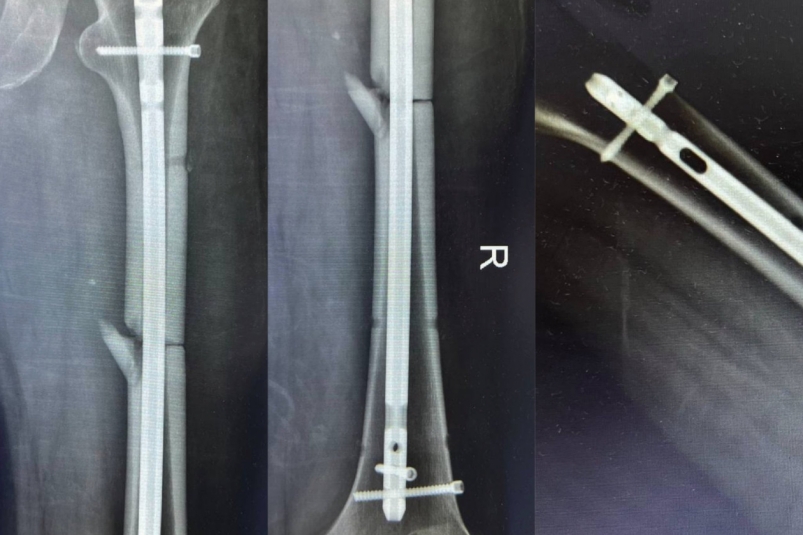

Stavropol.Media, 13 ноября 2025. Врачи в Ставрополе спасли 55-летнего мужчину, который упал с 7-метровой высоты и получил открытый перелом правого бедра со смещением костных отломков. Его экстренно доставили в городскую больницу скорой помощи в тяжелом состоянии, сообщается в Telegram-канале (18+) минздрава края.

"Специалисты обработали рану и стабилизировали состояние пациента. Врачи провели интрамедуллярный блокируемый остеосинтез бедренной кости. Методика обеспечила прочную фиксацию отломков", — говорится в сообщении.

Оперировали пациента завотделением сочетанной травмы Артур Апагуни, врачи-травматологи Виктор Посух и Михаил Даньшин. Сейчас пациента готовят к выписке.